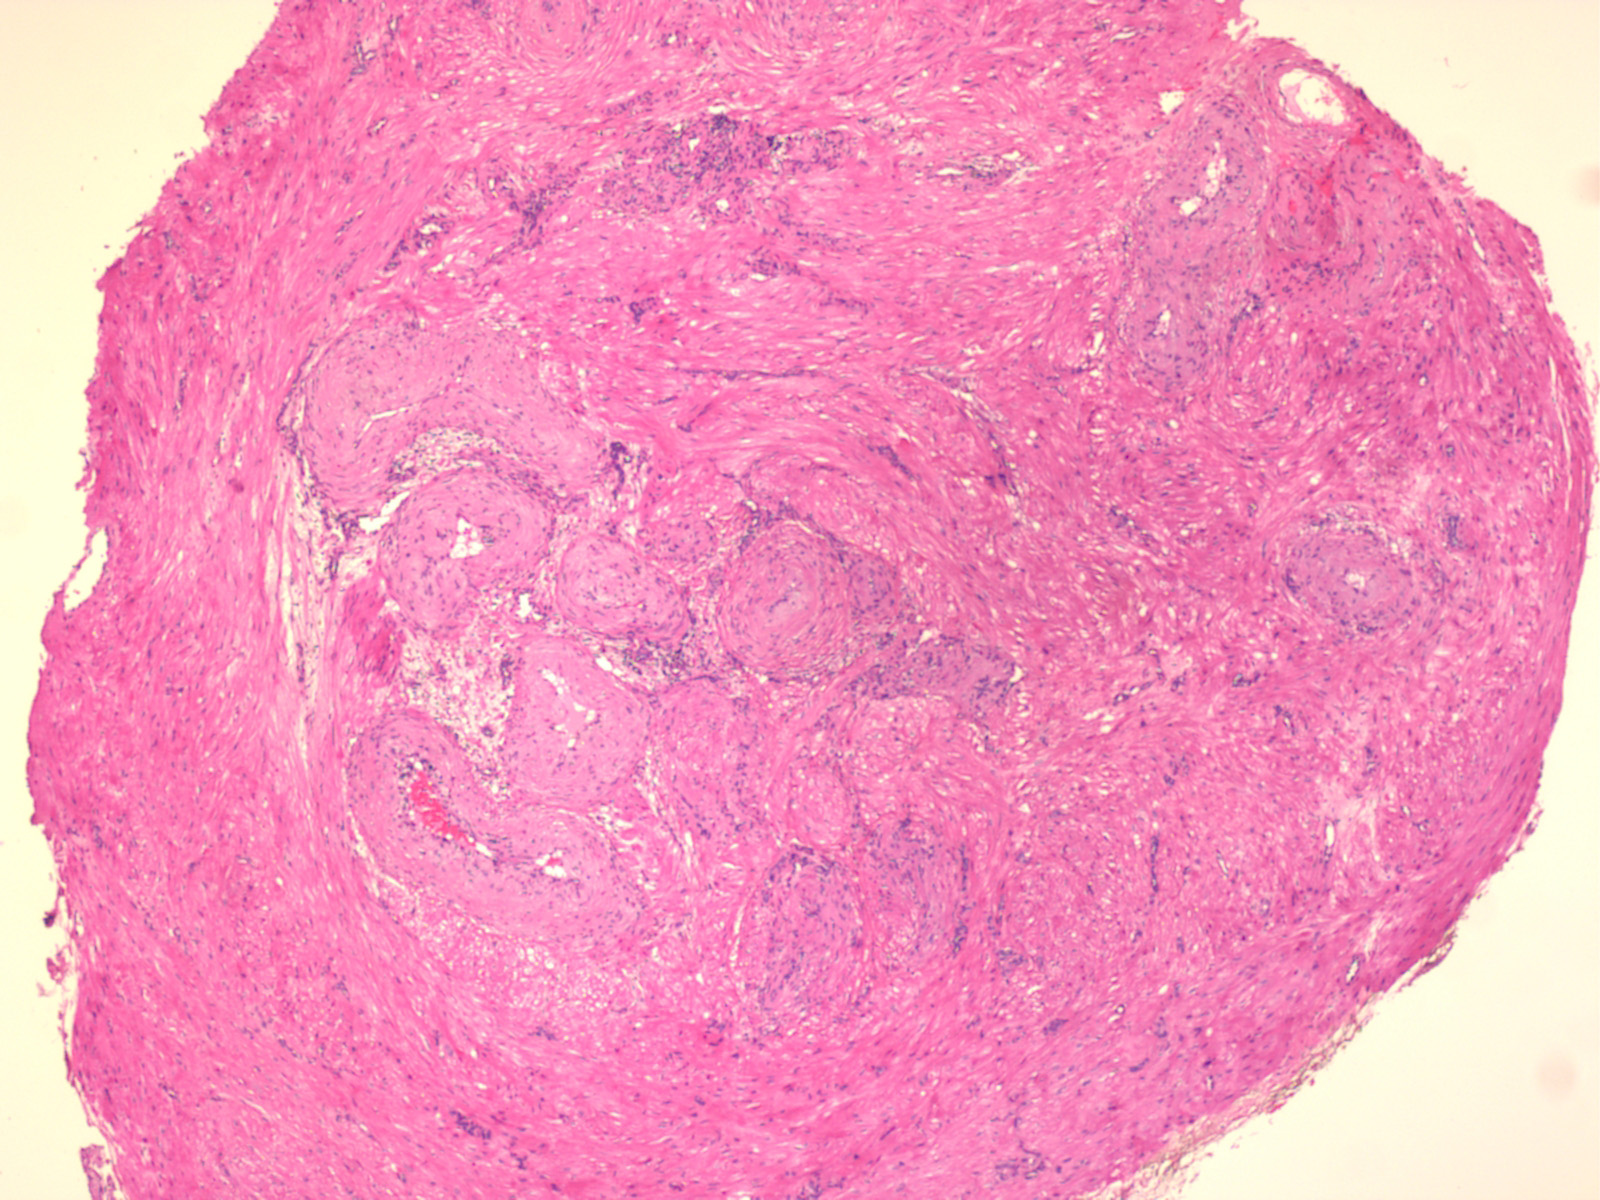

Angioleiomyoma =العضلوم الوعائي